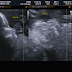

Quando o médico colocou aquele aparelinho na minha barriga, a primeira coisa que ele disse foi: "É um machinho!!!" Fiquei surpresa com a rápidez e emocionada, afinal, Igor você queria mesmo era nos mostrar quem estava chegando né, com direito a jóinha para curtir no facebook!

Quanta emoção meu filho, nem nasceu e já nos traz tantas alegrias, até o dedinho de rock você fez para agradar o papai, e os pézinhos que gostosos, não vejo a hora de te-los em minhas mãos.